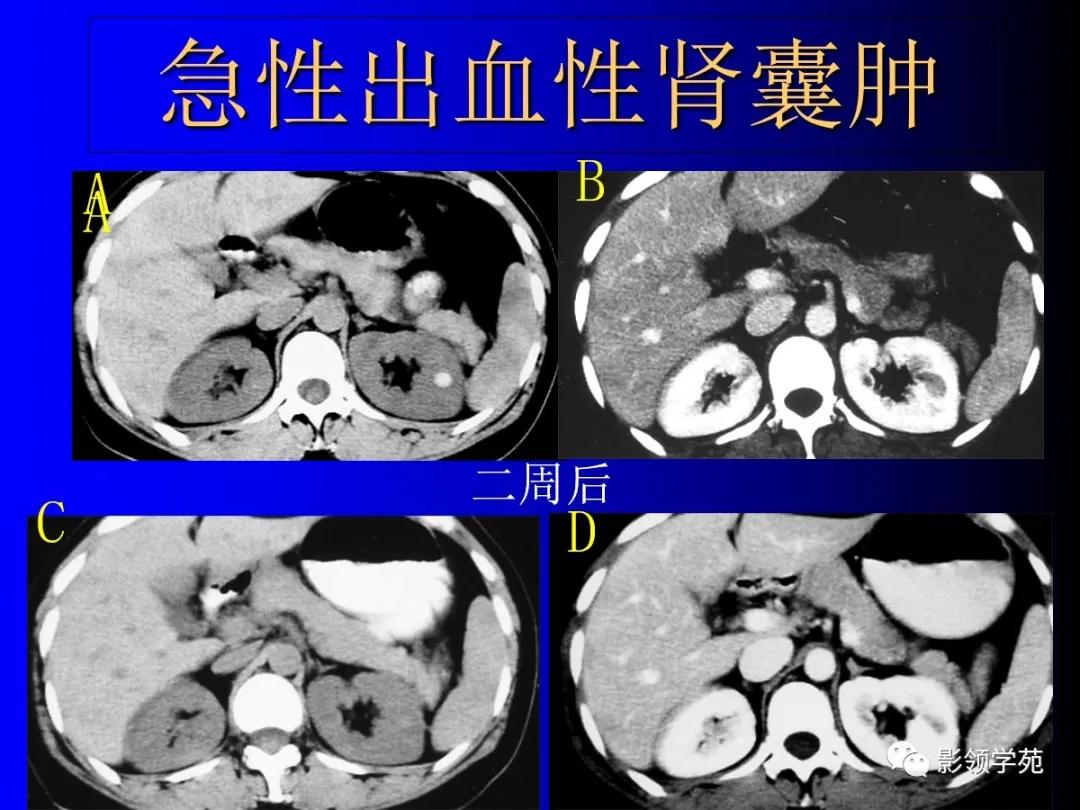

2、复杂性肾囊肿(Complicated cysts)

肾囊肿内含有血液、脓液、间隔或钙化

出血性囊肿。